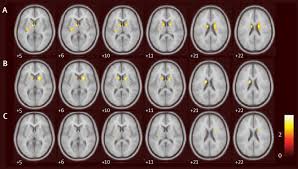

Diabetes Drug Exenatide Shows Promise Against Parkinson S Disease Medicine Sci News Com